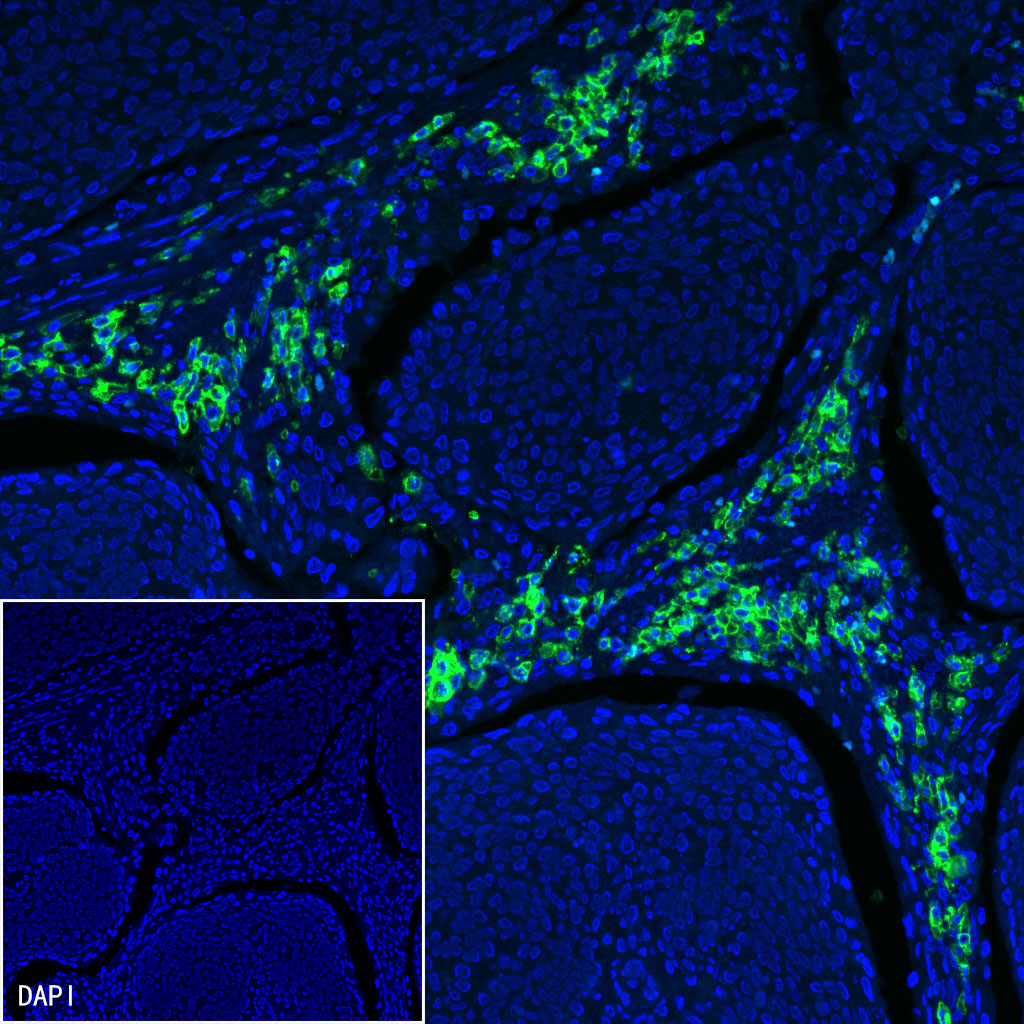

Immunofluorescence

IF shows positive staining in paraffin-embedded human colon cancer. Anti-CD38 antibody was used at 1/500 dilution (Green) and incubated overnight at 4°C. Goat polyclonal Antibody to Mouse IgG - H&L (Alexa Fluor® 488) (S0B4017) was used as secondary antibody at 1/500 dilution. Counterstained with DAPI (Blue). Heat mediated antigen retrieval with EDTA buffer pH9.0 was performed before commencing with IF staining protocol.

IF shows positive staining in paraffin-embedded human cervical squamous cell carcinoma. Anti-CD38 antibody was used at 1/500 dilution (Green) and incubated overnight at 4°C. Goat polyclonal Antibody to Mouse IgG - H&L (Alexa Fluor® 488) (S0B4017) was used as secondary antibody at 1/500 dilution. Counterstained with DAPI (Blue). Heat mediated antigen retrieval with EDTA buffer pH9.0 was performed before commencing with IF staining protocol.